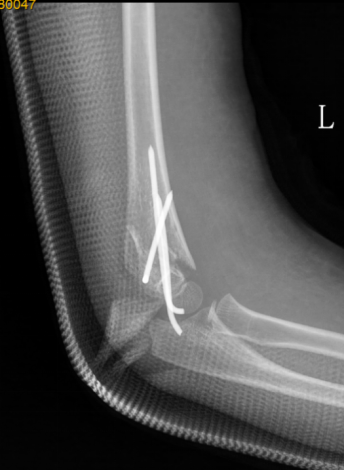

1、小红(化名):女、6岁、吊单杠时不慎摔伤致左肘部肿痛、畸形、活动受限2小时就诊我院。(下图为患儿术前X线片及CT检查)

此种类型的骨折称为肱骨髁上骨折,在完善相关辅助检查后予行麻醉下平乐郭氏手法正骨经皮钢针内固定治疗,术后患儿恢复良好,手术部位只有几个小针眼。(下图为患儿术后X线片)